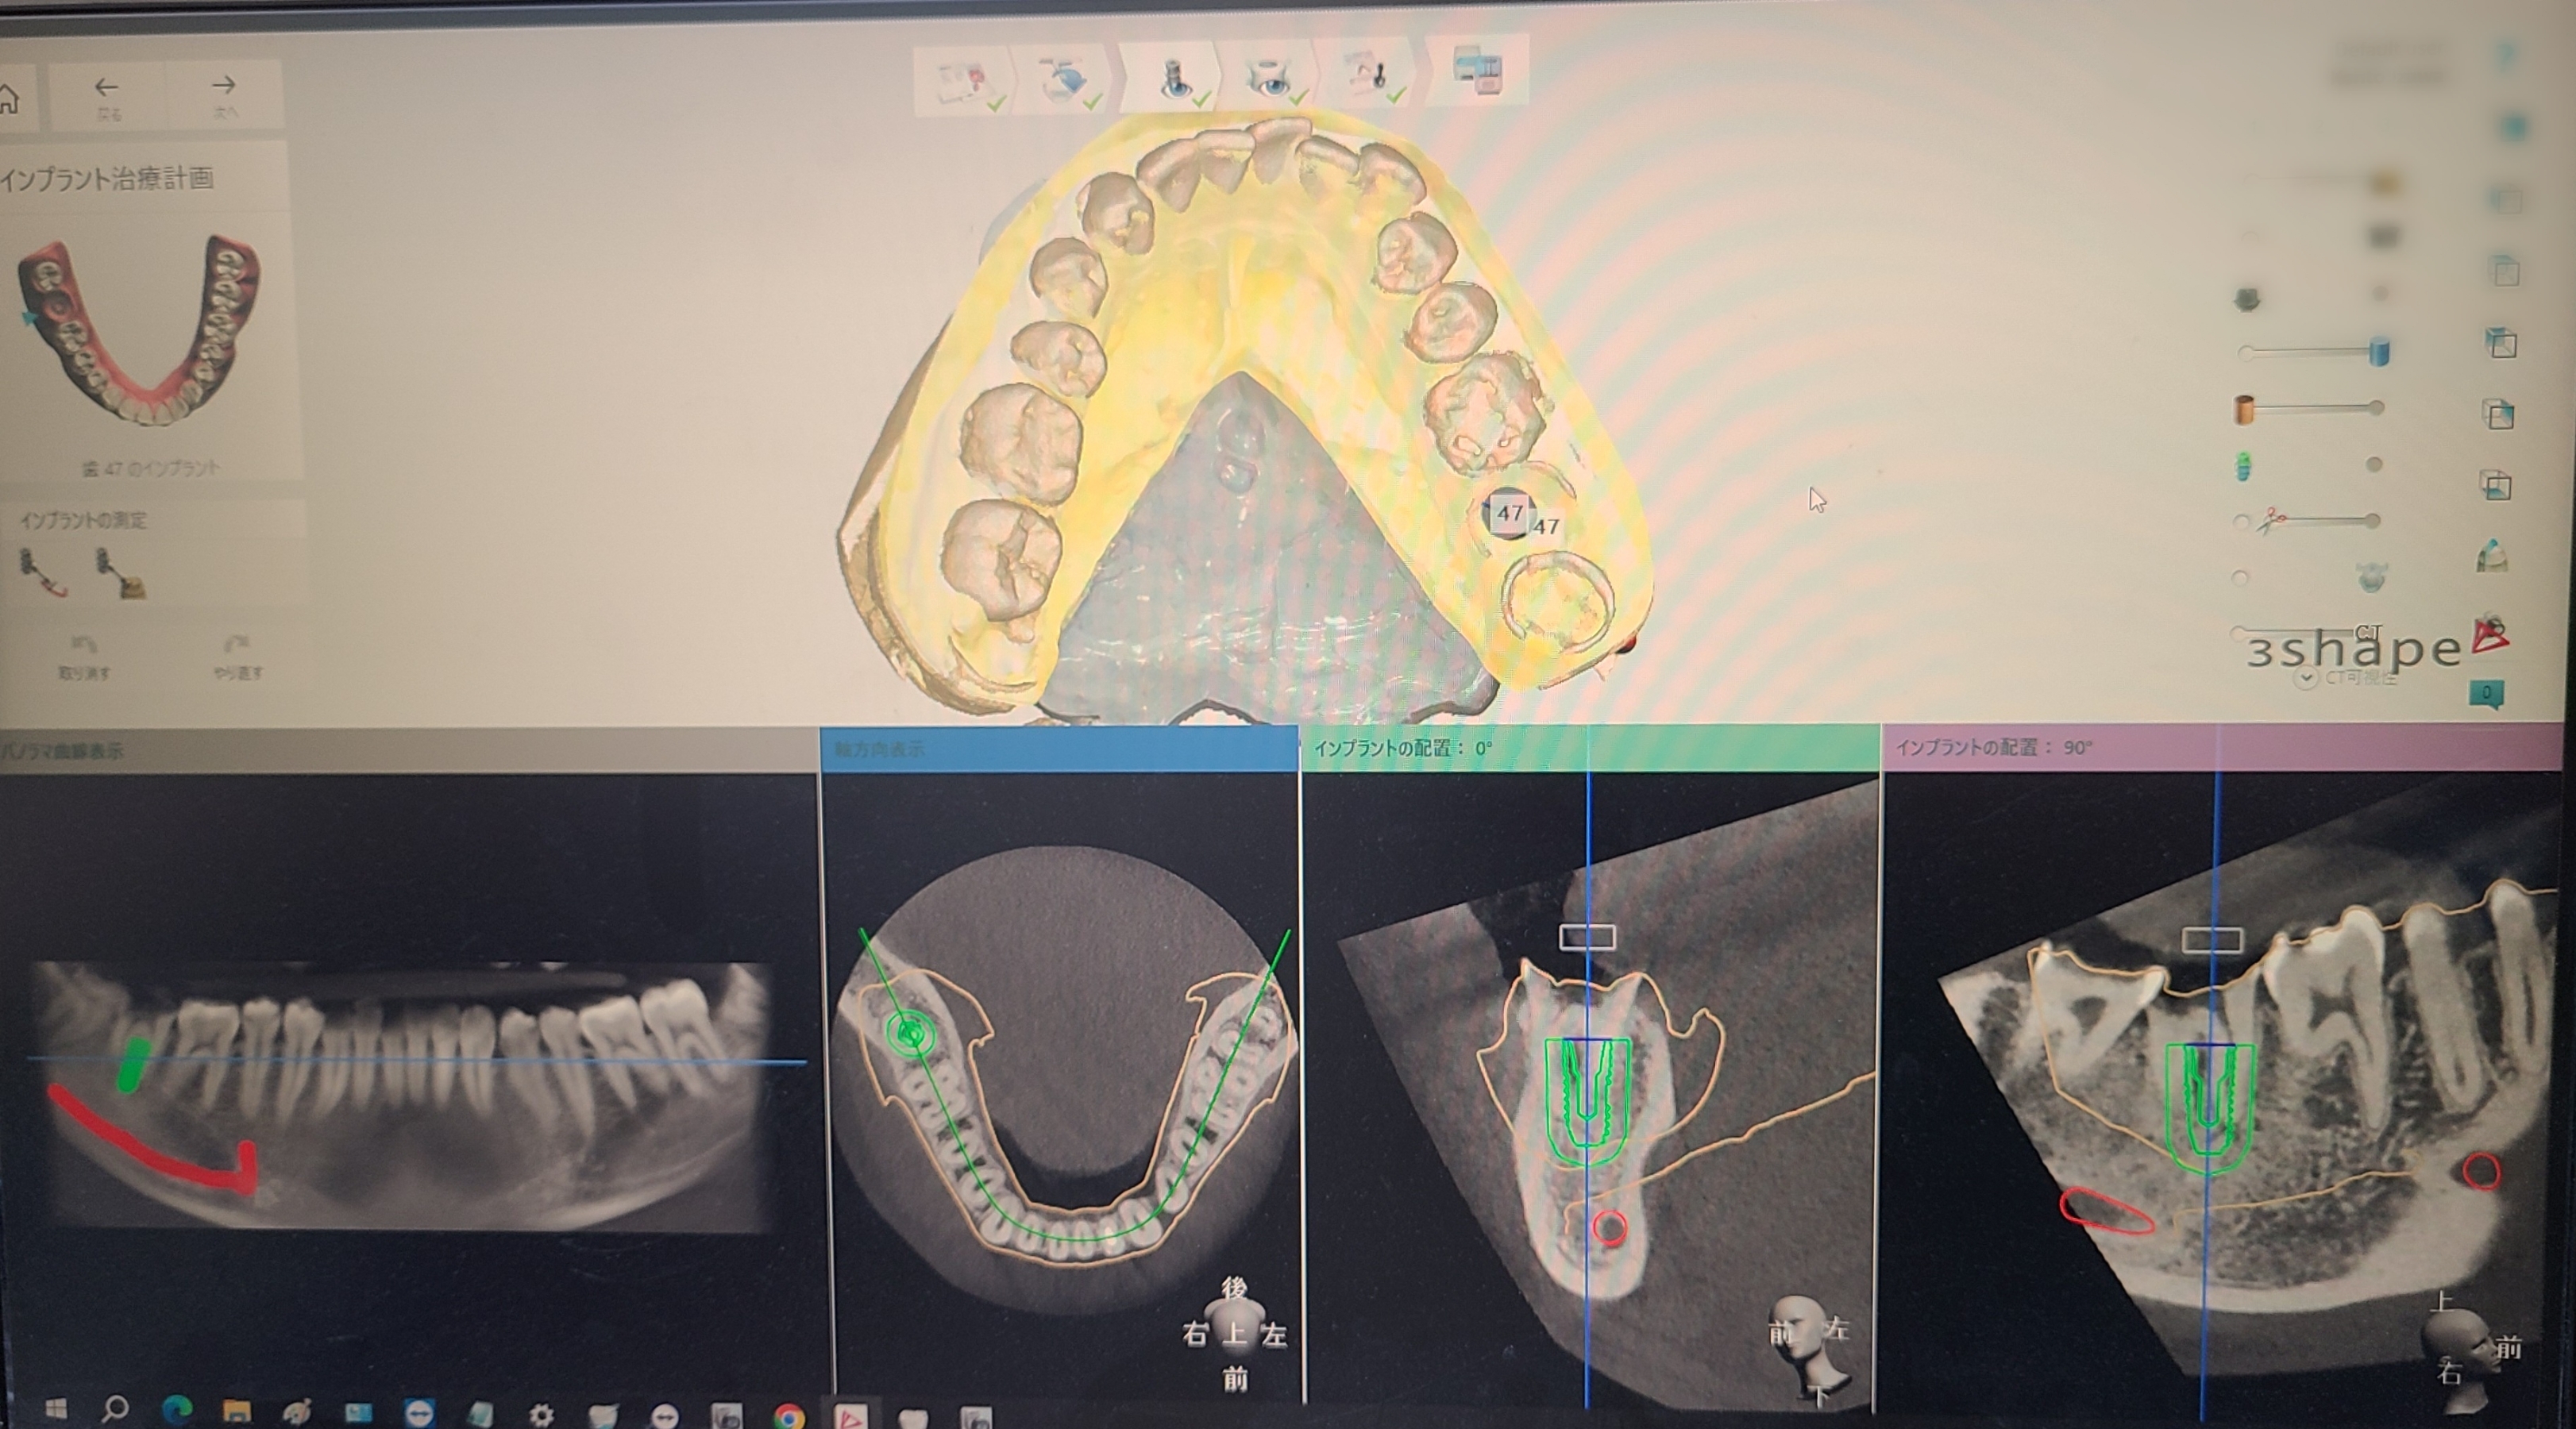

インプラントオペには患者様ごとにガイドを作成し使用しています

撮影したCTデータをもとにオペの治療計画をたて院内技工所で患者様ごとに、どこにどれくらいの長さのインプラントを埋め込むかの設計をしそれにあったガイドを作成しています

患者様ごとにガイドを作成することで安全で予知性の高いインプラント手術を可能にし、インプラントを骨に埋め込むためにかかる時間が短縮されることで術後の痛みや腫れを軽減し、治癒期間を短縮できます

2. コンピューター上で治療を計画

院内技工所でCT撮影データーから得られた情報を基に、神経や太い血管を避けながらインプラントの埋め込み位置院長とを計画します。

埋め込むインプラントのサイズや、角度、深さ等をソフトウェアでシュミレーションしますガイドを作成していきます